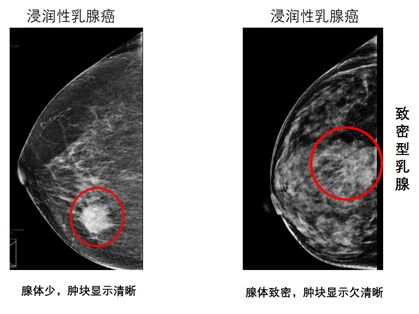

但乳腺X线检查对结节的检出却要受乳房腺体致密程度的影响,如果乳房内腺体少、脂肪多,那结节就容易显示;但如果腺体多、脂肪少,结节就不容易显示,甚至造成漏诊。而此时超声检查就可以弥补X线检查在致密型腺体中容易漏诊的不足。

所以乳腺癌的诊治指南都会建议对于乳腺X线检查提示致密型乳腺的女性人群,需要乳腺X线检查联合超声检查来提高乳腺癌筛查的敏感度。而乳腺磁共振检查可作为乳腺X线检查、乳腺临床体检或乳腺超声检查发现的疑似病例的补充及进一步检查,以及参与乳腺癌高危人群的筛查。